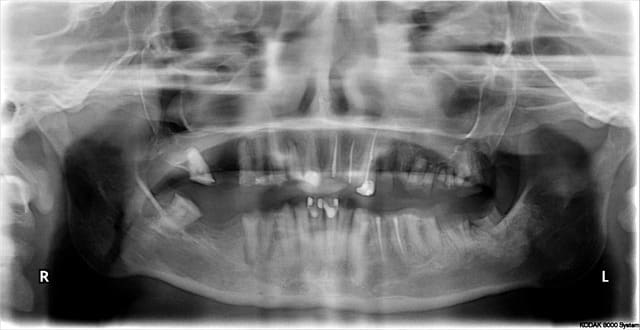

Patient perdu de vue pendant 1 an seulement après son ttt paro. Pffff.

Non, juste un paquet d'extractions des dents non conservables à l'époque, et un débridement radiculaire non chirurgical. La réévaluation était prévue à 2 mois avant d'éventuellement aller plus loin. En dépannage, et pour éviter l'adjointe, j'avais collé la couronne de la 11 aux voisines.

C'est sûr, ma "motivation" du patient est un échec total. Il me dit qu'il est "habitué, maintenant" à la situation. On verra s'il s'habitue aussi bien au complet bimax.